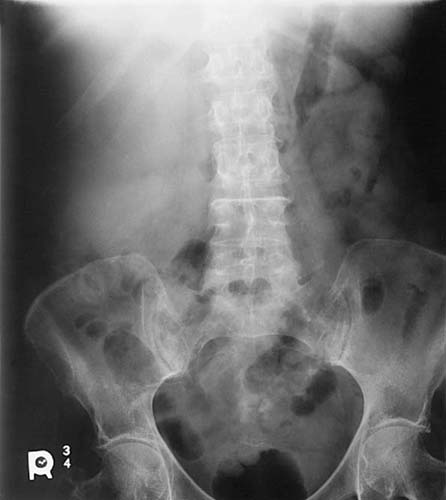

Radiographic contrast is the combined result of multiple factors associated with the anatomic structure, radiation quality, image-receptor capabilities, computer processing, and display. Subject contrast refers to the absorption characteristics of the anatomic tissue imaged and the quality of the x-ray beam. Differences in tissue thickness, density, and effective atomic number contribute to subject contrast (Fig. 3-19). For example, the chest is composed of tissues that vary greatly in x-ray lucency, such as the air-filled lungs, the heart, and the bony thorax. This anatomic region creates high subject contrast because the tissues attenuate the x-ray beam very differently compared with the abdomen for the same beam quality. When the thorax is imaged, great differences in brightness levels are recorded for the varying tissues (Fig. 3-20). The abdomen is composed of tissues that attenuate the x-ray beam similarly and is considered to be a region of low subject contrast. The brightness levels representing the organs in the abdomen are more similar (Fig. 3-21). Therefore, it is difficult to distinguish the stomach from the kidneys. As previously discussed, the quality of the x-ray beam also affects its attenuation in tissues, which alters subject contrast. Increasing the penetrating power of the x-ray beam decreases attenuation, reduces absorption, and increases x-ray transmission, resulting in fewer differences in the brightness levels recorded in the radiographic image.

FIG. 3-20 The thorax is an anatomic area of high subject contrast because there is great variation in tissue composition.

FIG. 3-21 The abdomen is an anatomic area of low subject contrast because it is composed of similar tissue types.